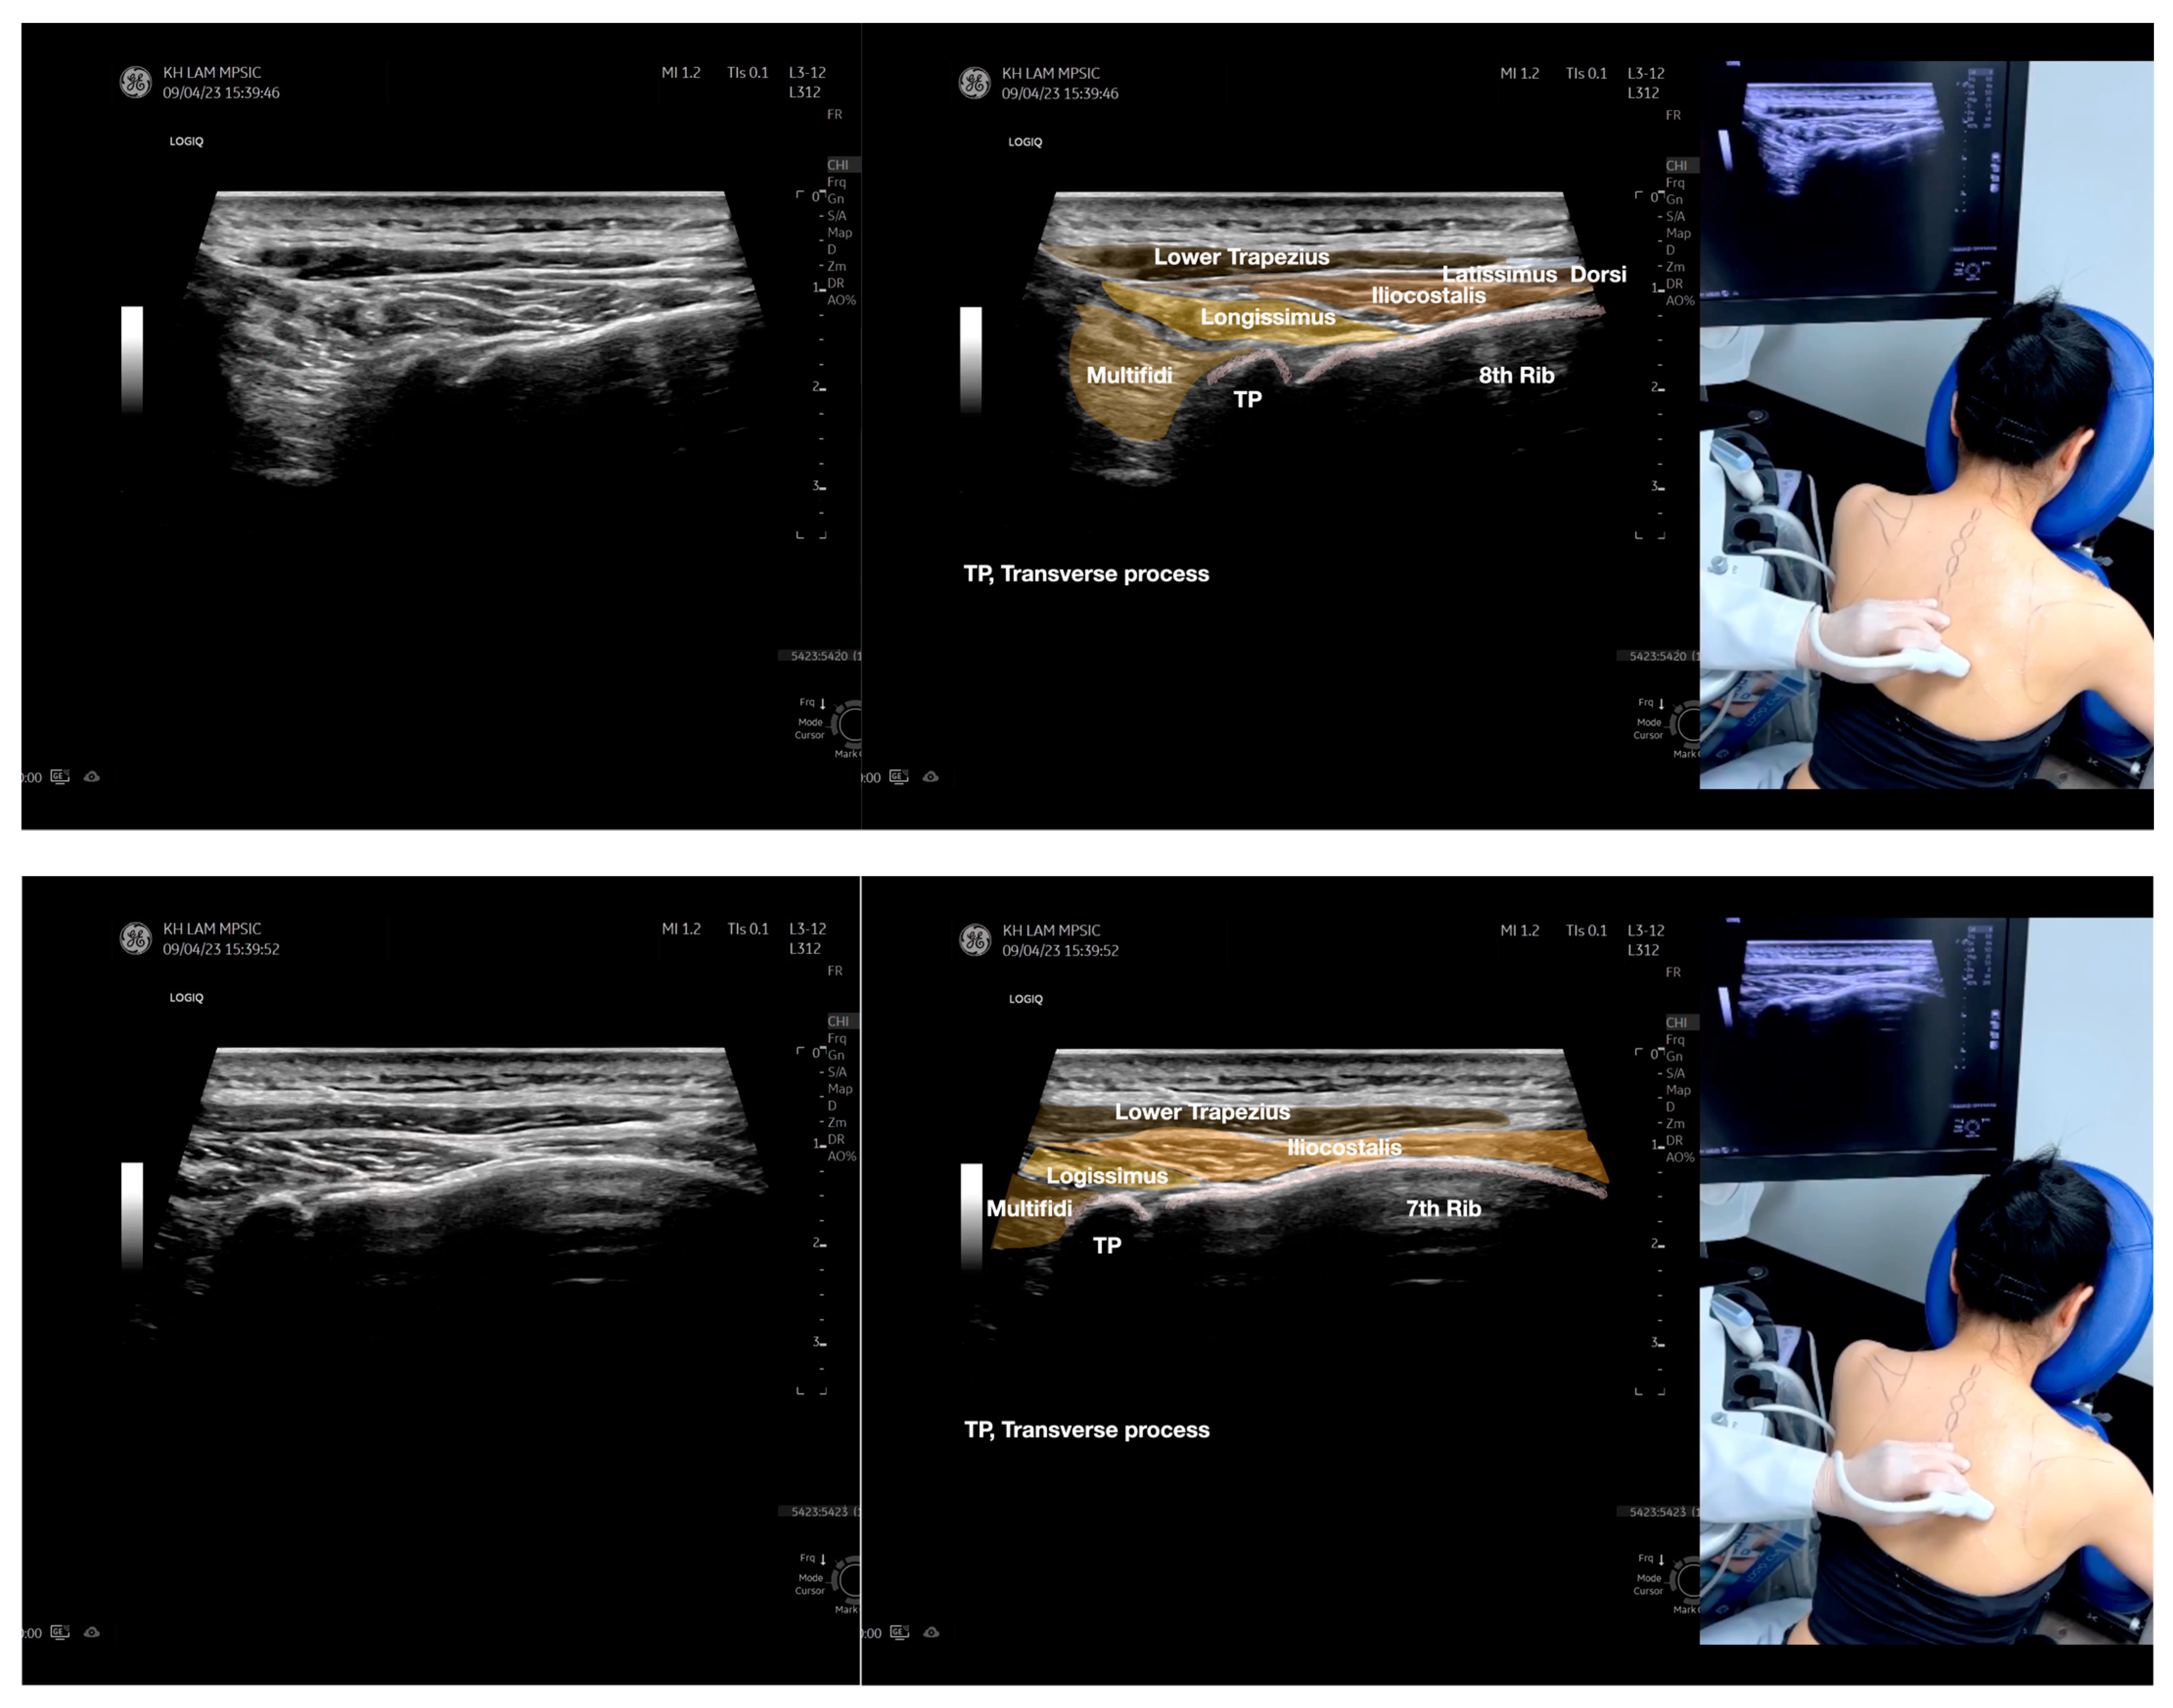

Figure 3.

Sonoanatomy of the lateral boarder of the scapular, its related muscles, and the infraspinatus fascia. Video S7 has demonstrated the step-by-step scanning techniques of these structures shown in this figure. Available online: https://www.dropbox.com/s/891m19vvw6bak34/Figure%203.docx?dl=0 (accessed on 1 January 2023).